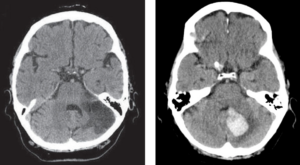

脳梗塞は動脈硬化によって脳血管が詰まった状態、脳出血は血管が破けて出血した状態です。小脳は体のバランスや手足の細かい動きをコントロールする役割があります。その部分に脳梗塞や脳出血が起こるとめまいだけではなく、ろれつが回らない、手足の痺れなどの神経症状がみられることが多いです。

椎骨脳底動脈は脳幹や小脳を栄養する重要な血管です。それらの血管が狭くなったり詰まったりして脳の血流が悪くなった状態です。このめまいは多彩で回転性のことも浮動性のこともあり、立ちくらみのように目の前が暗くなることもあります。MRIで脳の血管を撮影することが診断につながります。

当院ではめまいの性状、起こり方などの病歴を丁寧に聴取し診察を行い、めまいの種類や分類を可能な限り見極めることを大切にしています。危険なめまい(脳梗塞や脳腫瘍)を除外する目的で必要があればMRI検査も行えます。